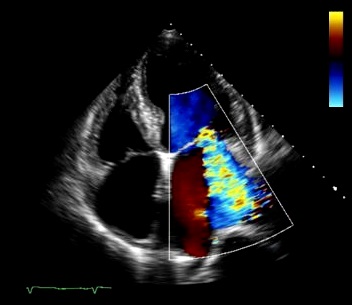

Explore real echocardiography case studies that provide practical insights and enhance your diagnostic skills.

Engage in learning experience using high-quality images to reinforce your knowledge and improve your diagnostic accuracy.

Welcome to the ultimate resource for those seeking to boost their echocardiography skills through in-depth case studies and real images. Dive into our cases studies and images designed to address your learning needs and elevate your diagnostic proficiency. Join us and unlock the echo tips and tricks and take your skills to the next level.

Adult Echocardiography Images